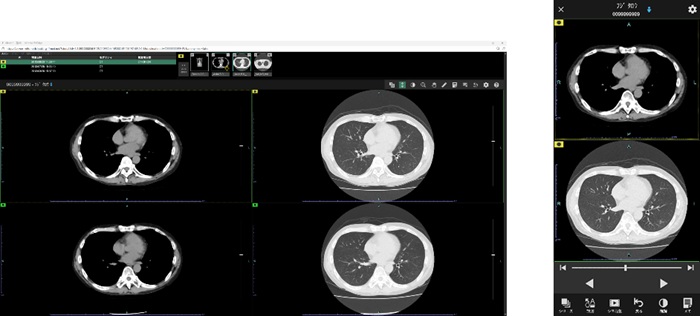

プリフェッチ機能など医用画像を高速に表示させる機能を搭載。標準ビューワには、「SYNAPSE SAI viewer(シナプスサイビューワ)」を採用した。利用者の好みに応じて操作性や表示画面を設定できる。画像配置を簡便に行える「レイアウティング機能」や、過去検査の画像と現在の画像を自動的に同期させる「自動スライス位置合わせ機能」などのワークフロー支援機能も備える。

「Cloud viewer(クラウドビューワ)」も利用できる。PCやタブレット端末などから、インターネット経由で、院外や移動中などでもCT、MRIなどの医用画像を参照が可能。専用ソフトのインストールが不要で、モバイル端末の標準搭載ウェブブラウザーで閲覧できる。端末に画像データを残さないゼロフットプリント方式を採用した。